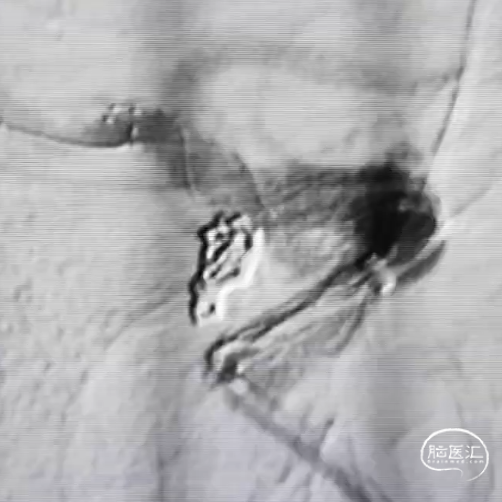

支架 4.5*23mm半释放,依次栓入通桥凤®弹簧圈 AEC-03-08-S、AEC-02-04-S*2、AEC-02-02-S。

造影见致密栓塞后,完全释放支架,结束手术。

从栓塞即刻效果看,国产通桥凤®弹簧圈栓塞顺畅,没有卡顿现象。国产通桥系列弹簧圈在此例动脉瘤栓塞中,成篮、钻孔、填塞及首尾栓塞过程中均表现优异。对此类高风险动脉瘤栓塞安全有效。

该病例中,因为动脉瘤是出血动脉瘤,带子囊。弹簧圈选择性能稳定的通桥凤®弹簧圈。通过此例动脉瘤栓塞,显示通桥凤®弹簧圈成篮稳定,同时栓塞出血子囊过程中尤其表现完好,可以很好钻孔进入子囊,对子囊进行安全栓塞。填充圈填塞过程中,填塞、抗解旋及首尾栓塞过程中均变现优异。